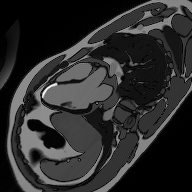

✅ SAX LGE – Correct Image Example:

Things to Look for in SAX LGE:

• Systematically assess all 17 AHA segments

• Document scar location, size, and transmural extent

• Compare with perfusion defects to identify hibernating myocardium

• Look for papillary muscle involvement